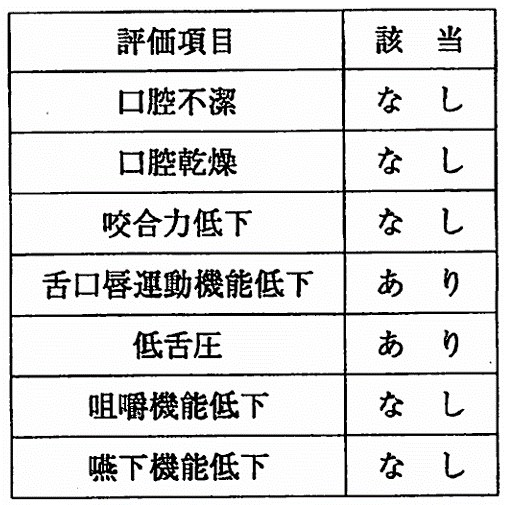

午前-110

70歳の男性。食べづらさを主訴として来院した。脳梗塞の既往がある。口腔機能低下症の検査結果を表に示す。適切な口腔機能訓練はどれか。2つ選べ。

a.舌抵抗訓練

b.アイスマッサージ

c.口唇の可動域訓練

d.バルーン拡張訓練

解答を見る

a.c